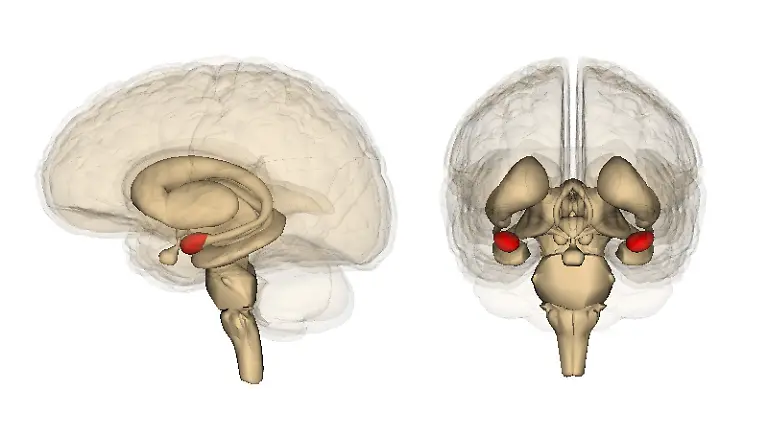

Egal, ob es ums Sehen oder Hören geht, ums Atmen, Sprechen, Rechnen oder Laufen: Stets sind es Milliarden grauer Zellen, die diese Fähigkeiten ermöglichen. Viele verschiedene Bereiche des Gehirns arbeiten zusammen, um die unterschiedlichsten Aufgaben zu lösen. Was wird von wo gesteuert? n-tv.de erklärt, was es mit Frontallappen, Mandelkern & Co. auf sich hat.